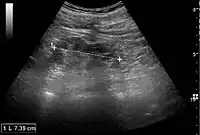

Ultrasound

Kidney ultrasonography is useful for diagnostic and prognostic purposes in chronic kidney disease. Whether the underlying pathologic change is glomerular sclerosis, tubular atrophy, interstitial fibrosis, or inflammation, the result is often increased echogenicity of the cortex. The echogenicity of the kidney should be related to the echogenicity of either the liver or the spleen (Figure 22 and Figure 23). Moreover, decreased kidney size and cortical thinning are also often seen and especially when disease progresses (Figure 24 and Figure 25). However, kidney size correlates to height, and short persons tend to have small kidneys; thus, kidney size as the only parameter is not reliable.[54]

Chronic renal disease caused by glomerulonephritis with increased echogenicity and reduced cortical thickness. Measurement of kidney length on the US image is illustrated by '+' and a dashed line.[54]